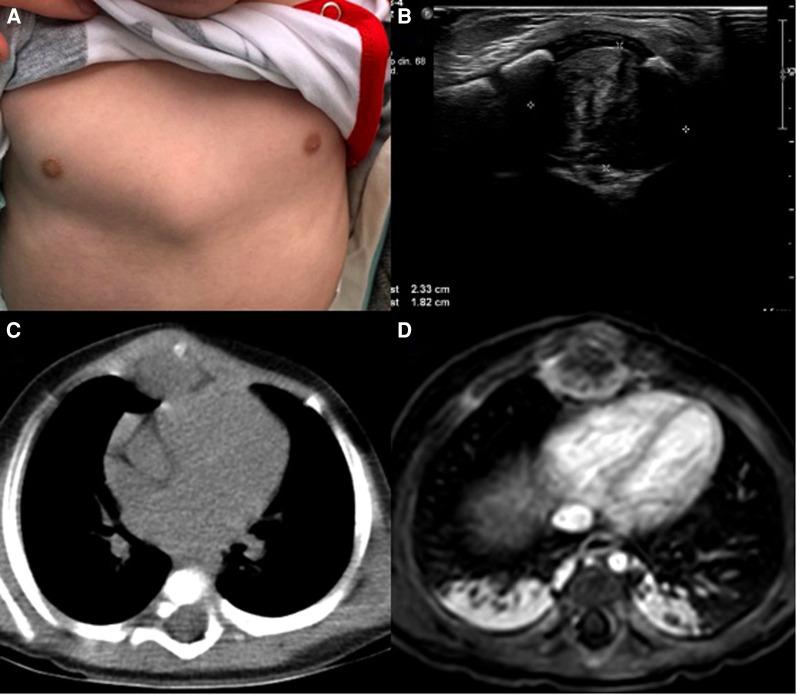

Case Report: Desmoid fibromatosis in the mediastinum of a 6-month-old toddler, what to do?

Desmoid fibromatosis is a rare, aggressive borderline lesion arising from soft tissues. Treatment will depend on the structures that the tumor has involved. Surgery with negative margins is the recommended strategy as it can usually achieve disease control; however, the tumor's location sometimes does not allow it. Therefore, a combination of medical therapies along with strict surveillance is crucial. We present the case of a 6-month-old boy with a chest mass. After further evaluation, a rapidly growing mediastinal mass involving the sternum and costal cartilage was detected. Desmoid fibromatosis was the final diagnosis.

韧带样纤维瘤病是一种罕见的、侵袭性的交界性软组织病变。治疗将取决于肿瘤所累及的结构。推荐的治疗策略是进行切缘阴性的手术,因为这样通常可以实现疾病控制;然而,肿瘤的位置有时不允许进行手术。因此,联合药物治疗并进行严格监测至关重要。我们报告一例6个月大患有胸部肿块的男婴病例。经过进一步评估,发现一个快速生长的纵隔肿块累及胸骨和肋软骨。最终诊断为韧带样纤维瘤病。